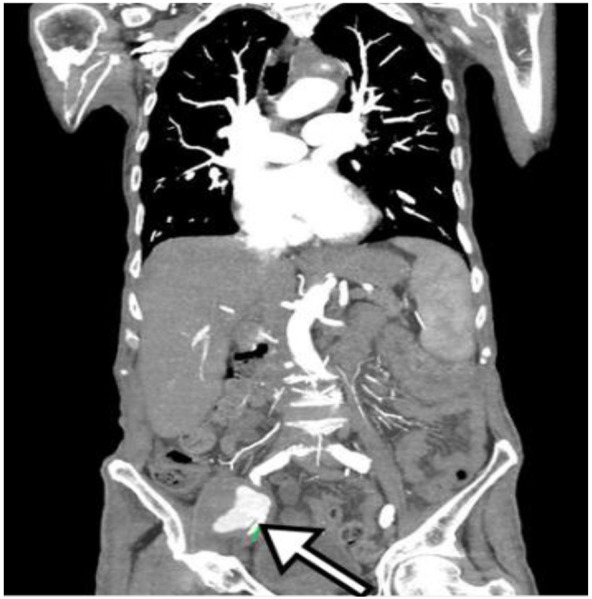

我们报告一例85岁男性膀胱腺癌病史,经17次膀胱内灌注卡介苗(BCG)治疗,表现出体质症状和多发假性动脉瘤:左侧锁骨下动脉、右侧髂外动脉和右侧股浅动脉。尽管没有最初的微生物学发现,血液和尿液培养最终培养出对吡嗪酰胺耐药的牛分枝杆菌BCG菌株。在微生物学证实之前,临床病程以进行性恶化和死亡为标志。本病例突出了膀胱内卡介苗治疗的一种罕见但严重的并发症,并强调了在卡介苗暴露后出现不明原因假性动脉瘤的患者早期怀疑和联合手术和抗菌治疗的重要性。